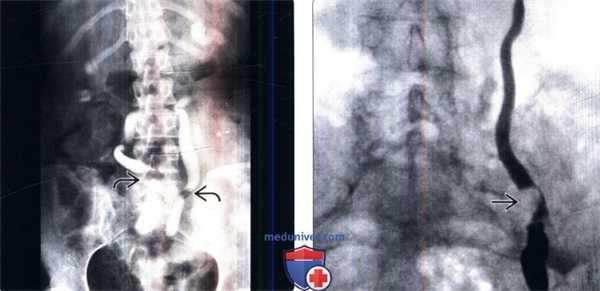

(Слева) Ретроградная пиелография: медиальное отклонение обоих мочеточников и их частичная обструкция. Данные визуализации характерны для забрюшинного фиброза. На КТ с контрастированием был подтвержден данный диагноз, поскольку был обнаружен ореол из ткани, окружающей аорту, нижнюю полую вену и дистальные отделы мочеточников.

(Справа) Ретроградная пиелография: эксцентричный дефект наполнения и стриктура дистального отдела мочеточника. Оба образования имеют неровную гладкую поверхность. Эти данные говорят о наличии стриктуры, вызванной злокачественным новообразованием, в данном случае - переходноклеточным раком.

• Сдавливает, вызывает обструкцию и медиально смещает мочеточники

• На КТ определяется мягкотканный ореол, сдавливающий аорту и нижнюю полую вену, распространяющийся по всей поясничной области